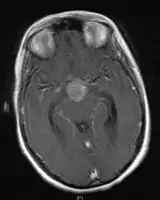

- Mainly located in midline structures, suprasellar region or pineal gland, also basal ganglia and hypothalamus

- Pineal Gland Germinoma

- Suprasellar Germinoma

- Current RT approach (1/11, PMID 20452141):

- Whole ventricular volume: 3rd, 4th, lateral, prepontine cistern

- Involved field volume: pre-chemotherapy volume + clinical margin 1-1.5 cm